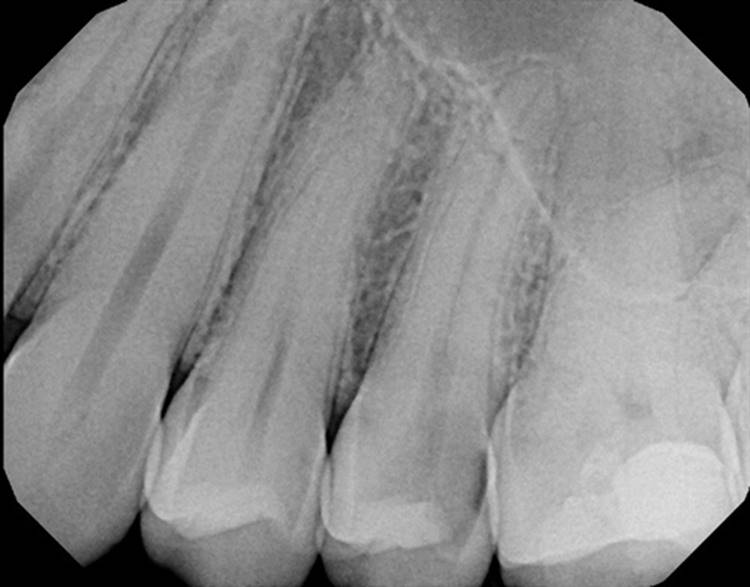

Forgive the sensor change from the first two cases to the last two. The good sensor broke and the back up isn’t as great.

EdgeFile® Cases